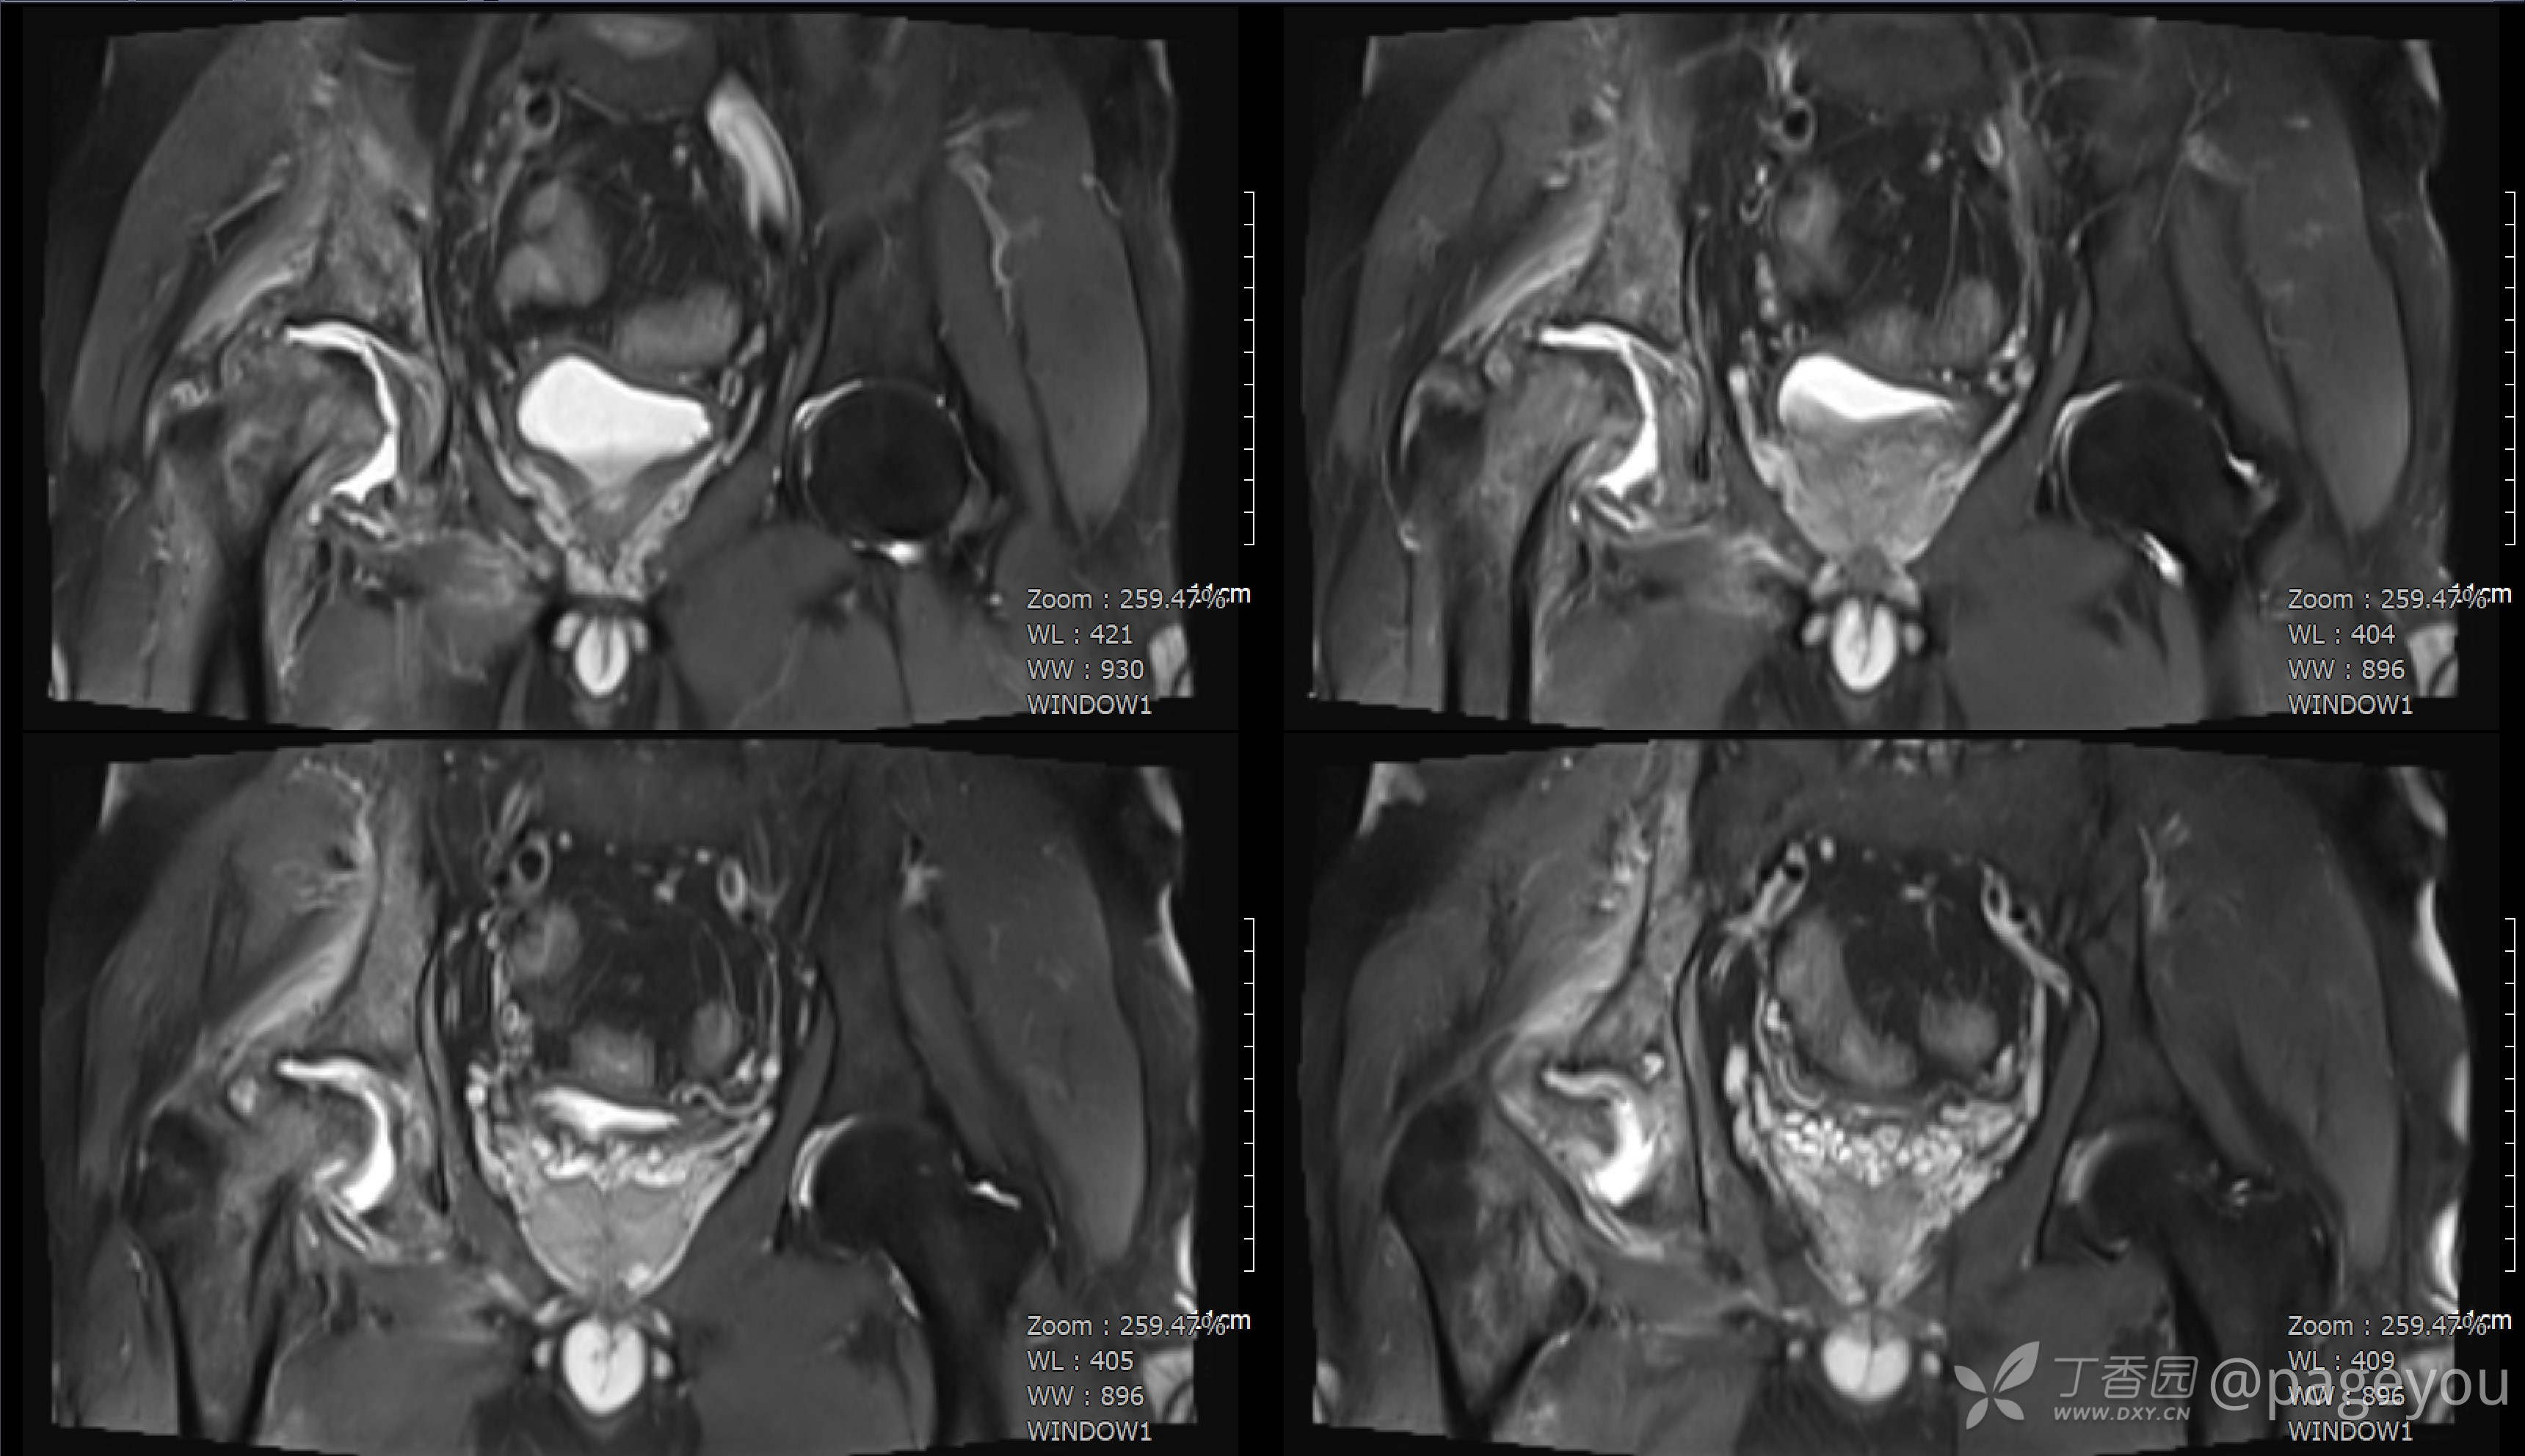

查骨盆MRI: